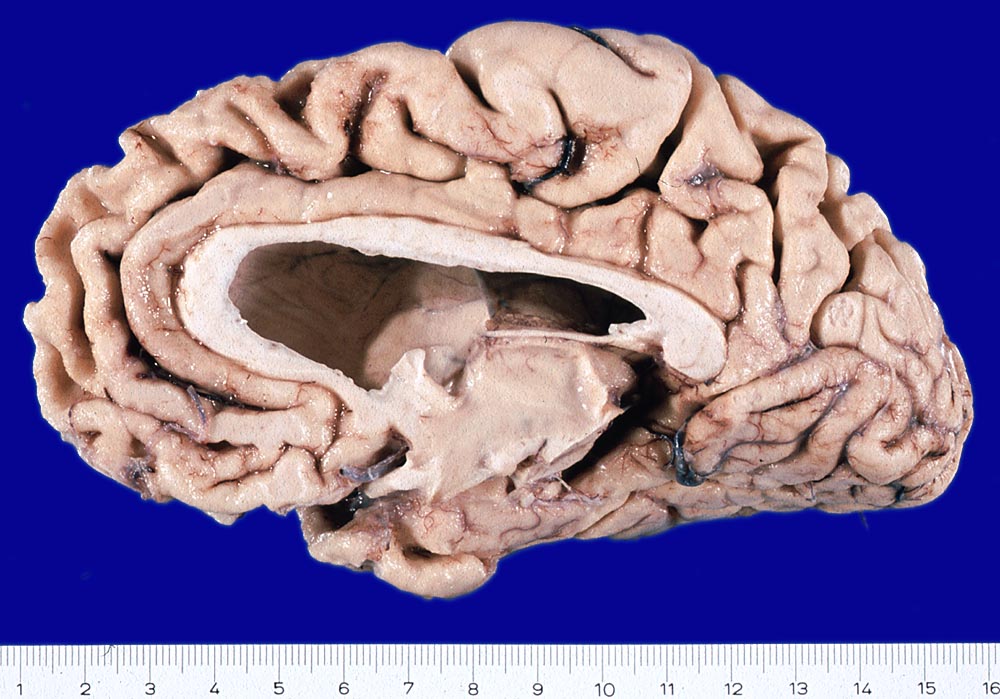

Gehirne von Alzheimer Patienten sind makroskopisch durch eine kortikale Atrophie (vor allem temporo-parietal) charakterisiert. Weiter findet sich meist eine deutliche Atrophie von Hippocampi und Mandelkernen. Diese geht einher mit einem Hydrocephalus internus (e vacuo), wobei vor allem die Temporalhörner der Seitenventrikel betroffen sind.